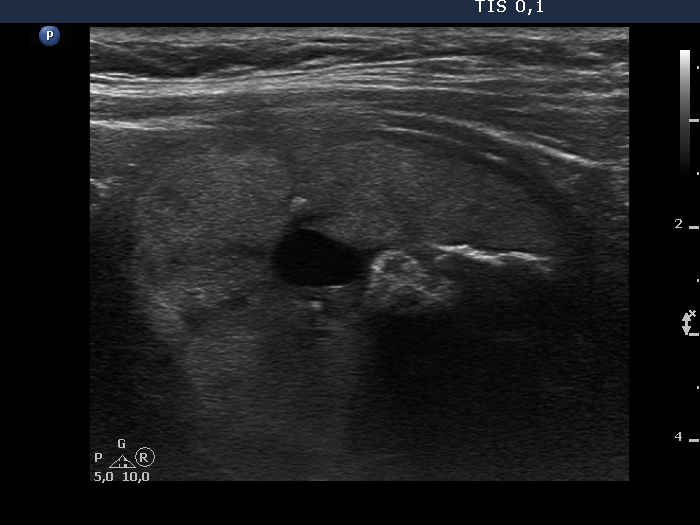

Benign cystic-colloid goiter (cytological diagnosis)

The hyperechogenic granules within the ventral solid part might be microcalcifications. The echogenic figures in the solid area cannot be the consequence of posterior enhancement because they are in front of the cystic area. Note that the nodule has in fact a moderately hypoechogenic solid part which seems to be echonormal dorsal to the cystic fluid because of the acoustic enhancement dorsal to the fluid.